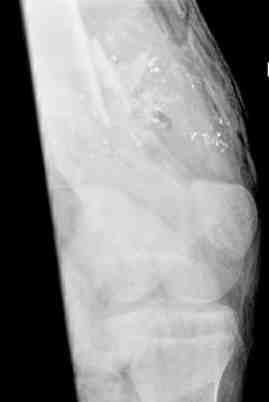

Представлены фотографии и рентгенограммы 21летней девушки, страдающей от bilateral leg malalignment syndrome. The next figure shows pictures and x-rays of 21 y.o. female with bilateral leg malalignment syndrome

Перед лечением. Before treatment

После деротации левого бедра и голени. After derotation osteotomy of lt femur and tibia

Результат The final result after derotation osteotomies of rt femur and tibia.

В верхнем ряду показаны рентгенограммы до, после коррекции и после снятия аппарата Илизарова. On the upper row the X-rays of lt leg before correction, after correction and after apparatus removal have been showed.

В нижнем ряду представлены два снимка после коррекции деформации правой голени. Видно, что качество коррекции не зависит от квалификационного наложения аппарата Илизарова, что было специально произведено для проверки работы программы. Lower two X-rays – rt leg after deformity correction. As you can see the quality of correction does not depend of placement of Ilizarov Apparatus